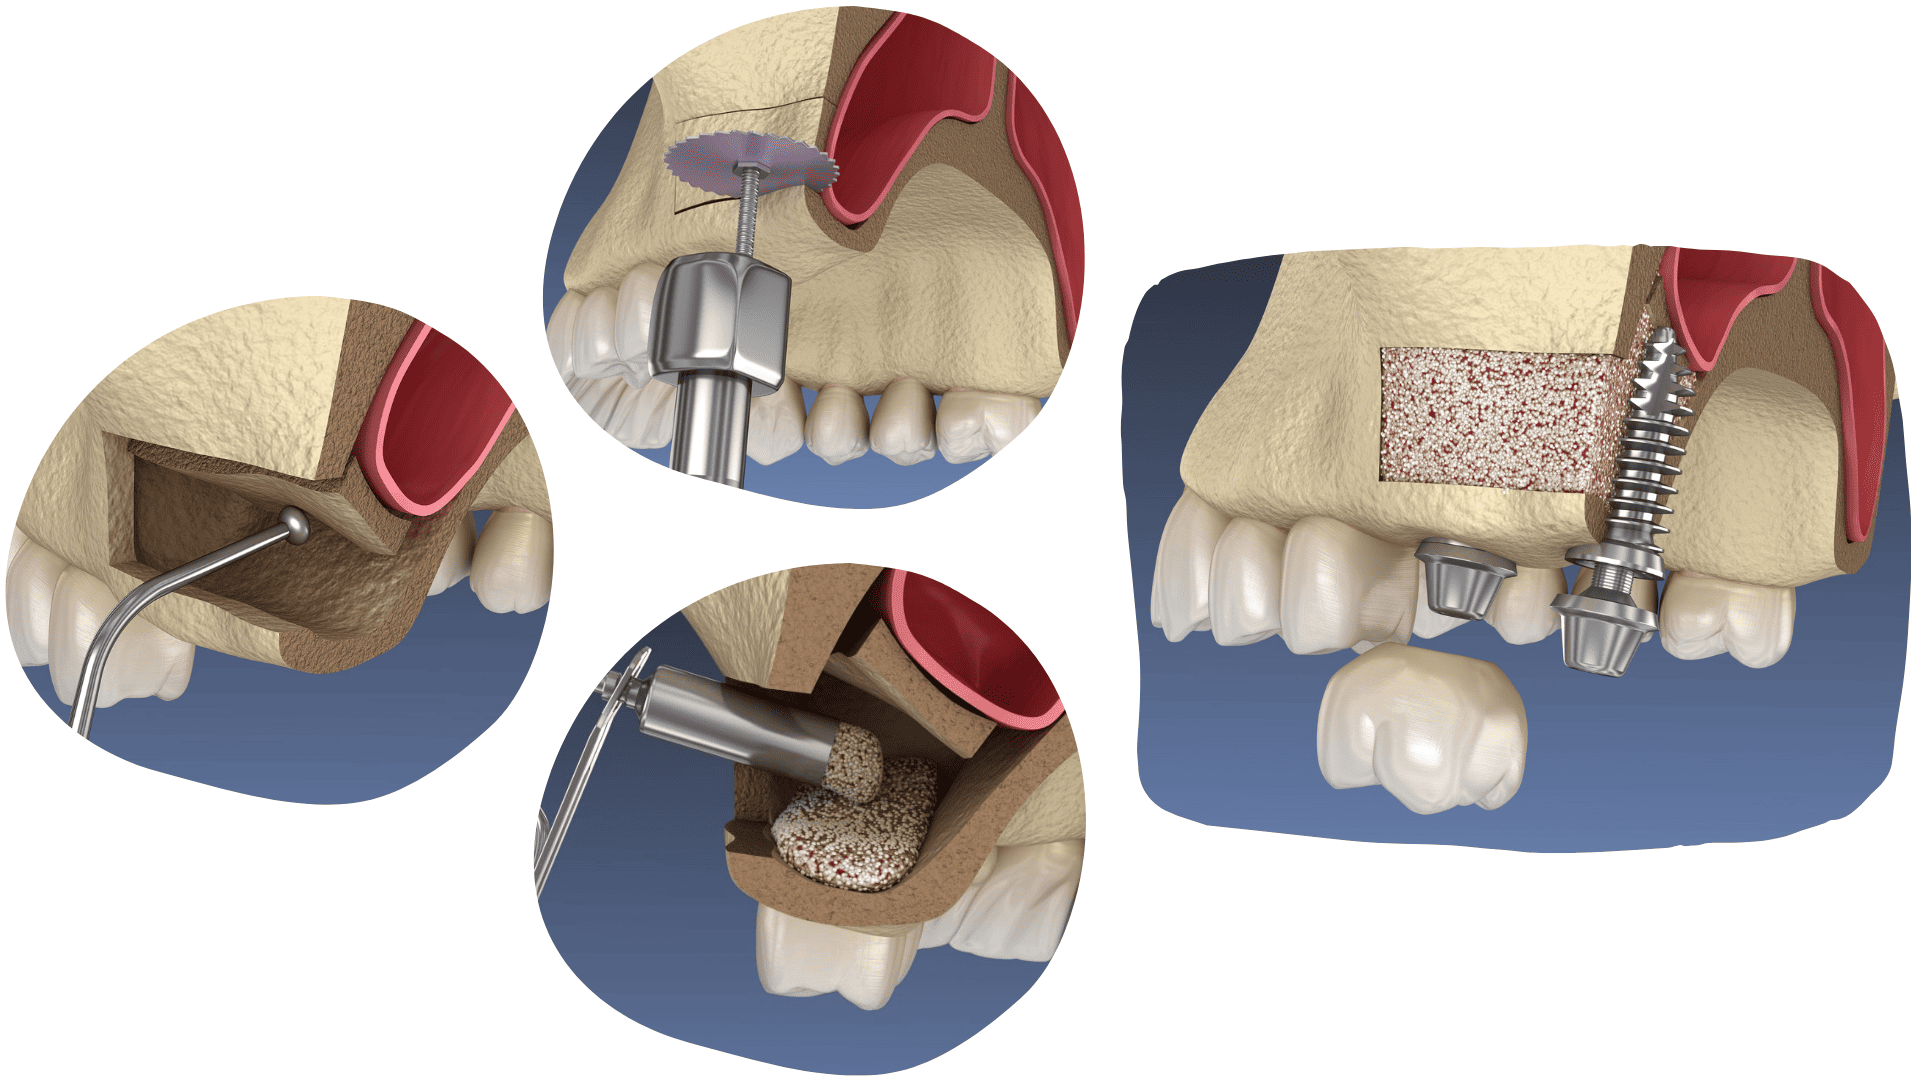

SINUS LIFT

Ako se izgubljeni zub ne nadomjesti na vrijeme, dolazi do gubitka čeljusne kosti, a sinusi zauzimaju prostor gdje je ona nekad bila, zbog čega nije moguće odmah ugraditi implantat i potrebno je napraviti sinus lift.

Sinus lift je oralno-kirurški zahvat kojim se podiže dno maksilarnog sinusa i dodaje umjetna kost kako bi se stvorila čvrsta podloga za ugradnju implantata.

Kod manjeg gubitka kosti implantat se može ugraditi odmah, istovremeno sa sinus liftom, dok je kod većeg potrebno pričekati da nova kost sraste i ojača.

Zahvat je bezbolan i izvodi se pod lokalnom anestezijom.